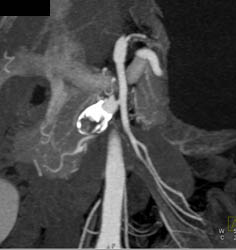

Hepatic Artery Aneurysm